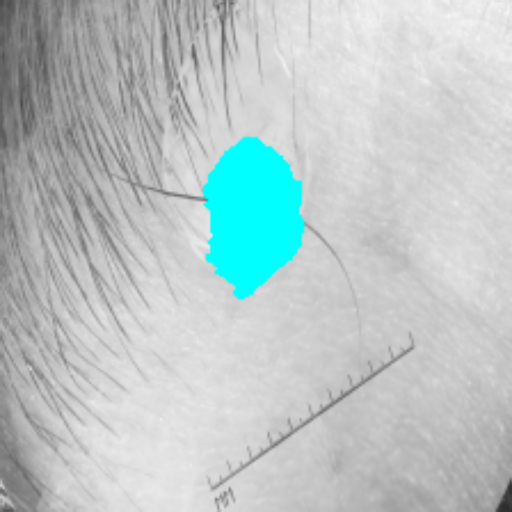

Figure 3 presents a qualitative comparison of segmentation performance on examples from the Synapse, BTCV, ACDC, and ISIC17 datasets. The first two examples (from Synapse) highlight variations in segmentation performance among U-Net, TransUnet, Mamba-Unet, and Swin-Unet. While Swin-Unet performs well in the first example, its performance decreases in the second example, particularly in segmenting the organ highlighted in blue. Additionally, it misclassifies background regions as the class highlighted in orange. In contrast, our approach demonstrates high robustness in segmenting all classes accurately and aligning well with the ground truth masks.

Refer to caption Refer to caption Refer to caption Refer to caption Refer to caption Refer to caption Refer to caption

Slice GT Unet TransUnet Mamba-Unet Swin-UMamba MambaCAFU-V1

Figure 3: Visual comparison of segmentation examples from Synapse (first two examples), BTCV (3-4 examples), ACDC (5th example) and ISIC17 (last example). Columns: input slice, ground truth, Unet, TransUnet, Mamba-Unet, Swin-UMamba, and MambaCAFU-V1.